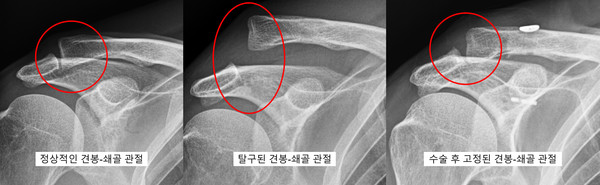

김두한 교수_ 위 그림처럼 어깨에는 2개의 관절이 있습니다. 쇄골과 날개뼈의 견봉과 만나서 이루는 1. 견봉-쇄골관절, 상완골과 날개뼈의 관절와 부분이 만나는 2. 관절와-상완 (glenohumeral) 관절이 있습니다.

관절와-상완관절 외에도 견봉-쇄골 관절도 탈구되는 경우가 흔히 있습니다. 예를 들어 옆으로 어깨가 땅에 부딫히면서 넘어지거나, 슛동작을 하려고 팔을 올릴 때 수비자가 강하게 팔을 내려치면 팔과 쇄골에 분리가 되려는 힘 (shearing force)을 받아 탈구가 발생하게 되게 됩니다.

견봉-쇄골의 탈구가 발생하면 쇄골을 잡아주는 중요한 인대들이 모두 파열되는 경우가 있습니다. 쇄골은 어깨를 들고 돌릴 때 견갑골을 강하게 잡아주어 지렛대 역할을 하게 되는데 탈구의 정도가 심하면 효과적인 힘의 전달이 되지가 않아 어깨 기능 장애를 초래할 수 있습니다. 그렇게 되면 수술로 다시 인대를 재건해 줘서 원래의 어깨 안정성을 회복시켜 줘야 합니다.